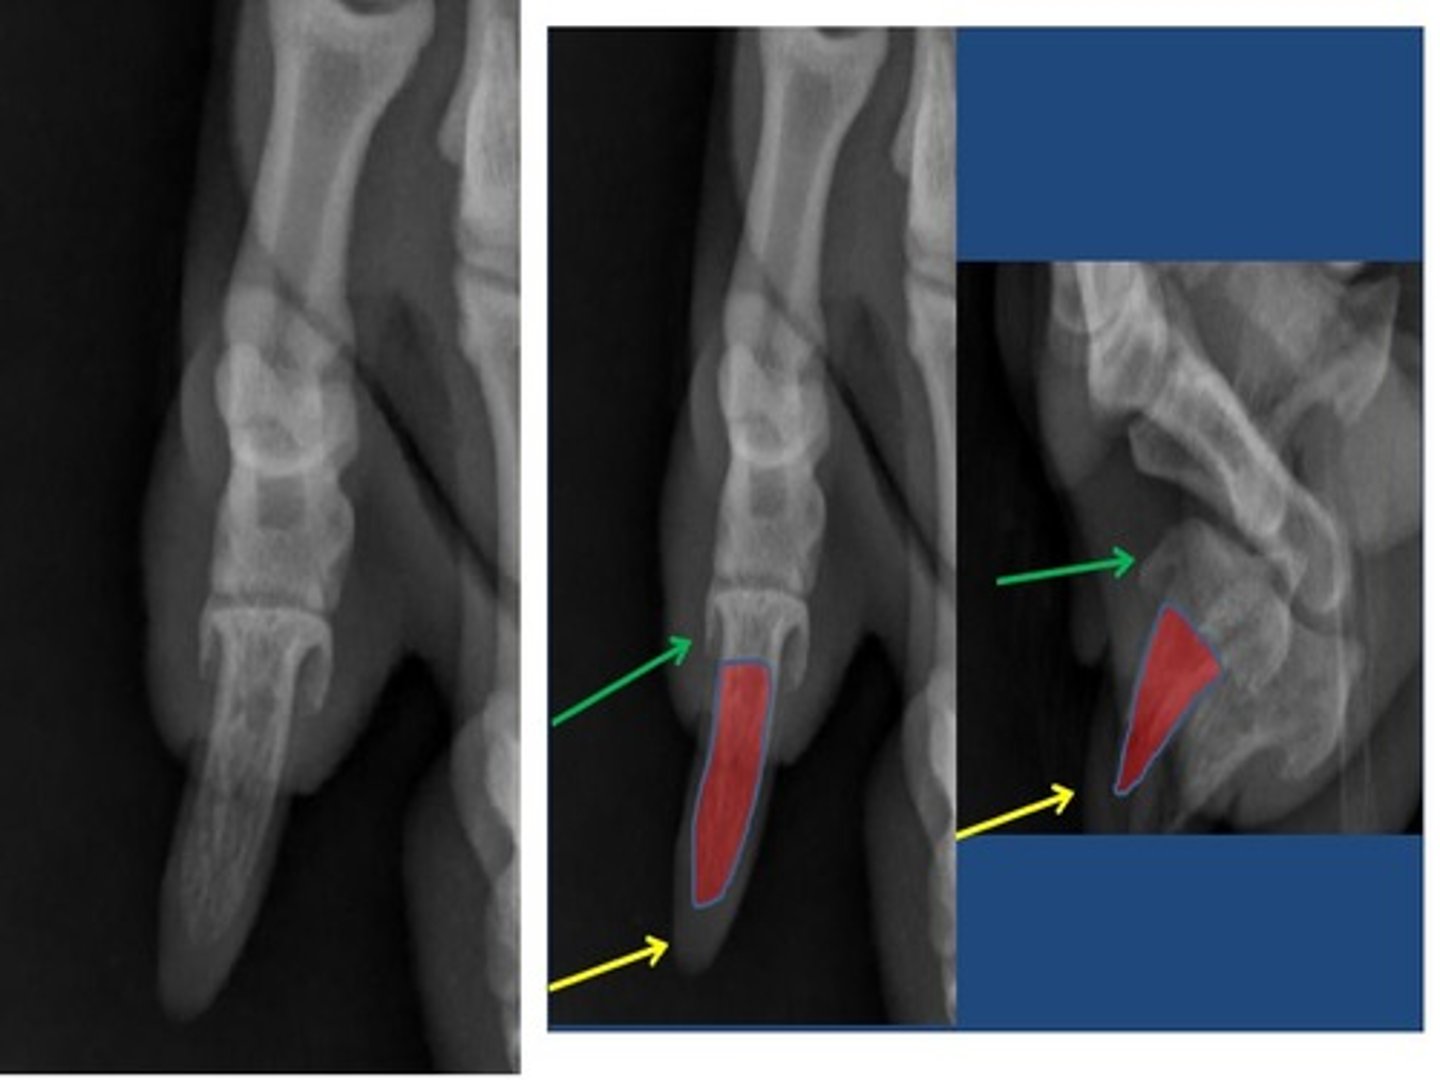

ungual crest

a think shelf of bone on the distal phalanx that overlaps the claw and forms a band of bone around the claw

(T)

<p>a think shelf of bone on the distal phalanx that overlaps the claw and forms a band of bone around the claw</p><p>(T)</p>

ungual process

a curved conical extension of the disatal phalanx into the claw

<p>a curved conical extension of the disatal phalanx into the claw</p>

flexor tubercle

small process on the palmar surface for insertion of the deep digital flexor tendon (#2)

<p>small process on the palmar surface for insertion of the deep digital flexor tendon (#2)</p>